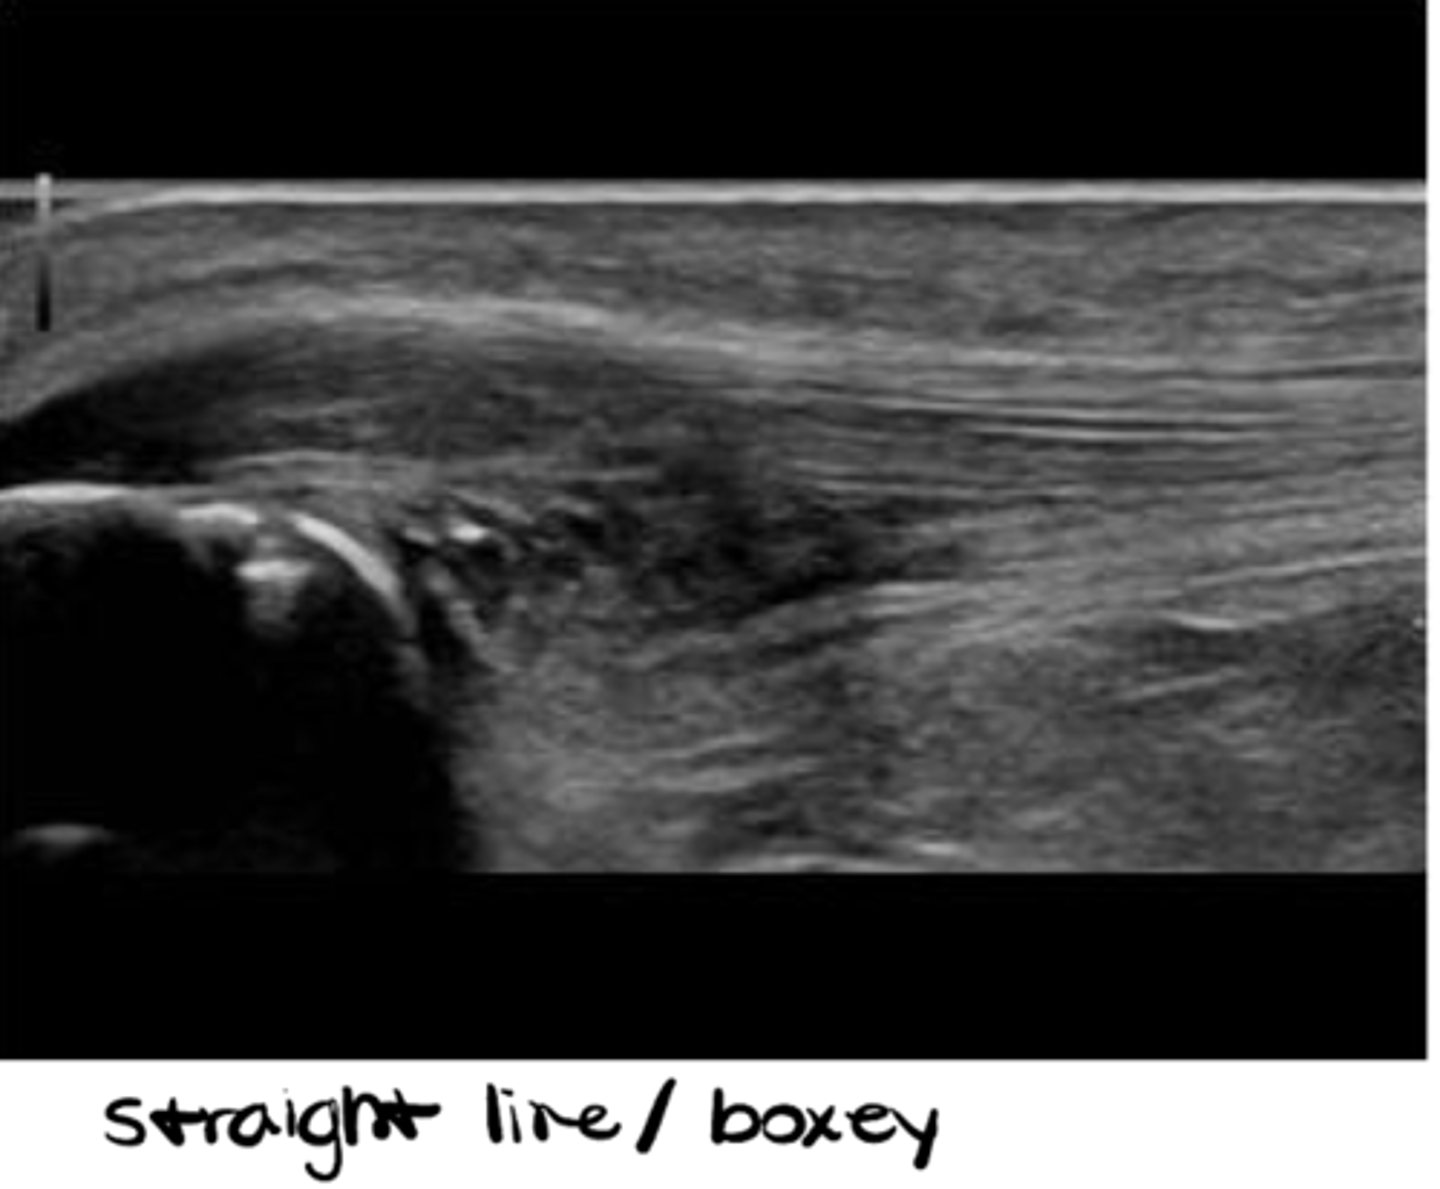

___________: mode of ultrasound that is STANDARD; sound waves bounce down --> bounce back --> give you a 2D image. It's dynamic, you can move it, and you can see the image change as you move the sound head, but it's like a picture -- it's ONE slice of a SMALLER area (ex: one portion of the quadriceps)

B-Mode (2D Mode/Greyscale)

Which type of probe is MOST appropriate to view superficial structures?

Linear with the HIGHEST frequency -- used 99% of the time